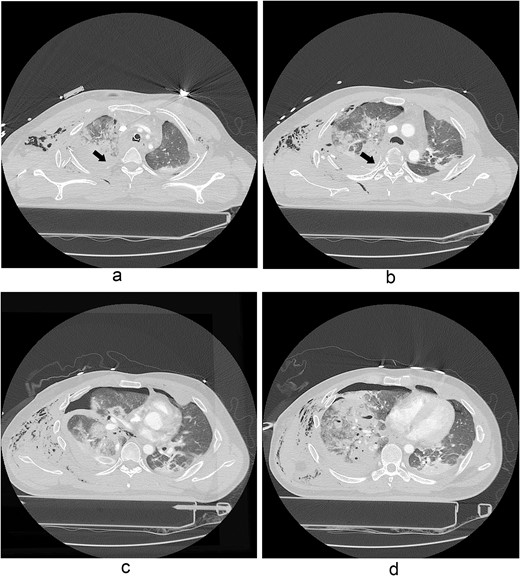

A 31-year-old unconscious male was in an unwitnessed accident when a car hit the motorcycle he was driving. A rescue team transported him to the emergency department. Clinical examination revealed hypoxia with SpO2 at 85%, tachycardia at 126 bpm, hypotension of 69/58 mmHg, and hypothermia at 35.8°C. Initial arterial blood gas analysis (ABGA), pH, PaO2, and pCO2 were 6.92, 49, and 58, respectively. Chest X-ray showed right hemopneumothorax, mediastinal shifting, and multiple bilateral rib fractures (Fig. 1). A right-side closed thoracostomy was performed. The chest drainage of 1 L was bloody. Chest computed tomography (CT) showed fractures in the right ribs 1 to 9 and left ribs 1 to 7, as well as lung contusions, multiple lung lacerations, right hemopneumothorax, and active hemorrhage in the right upper and lower lung lobes (Fig. 2). Brain and abdominopelvic CT showed no organ injury. An emergency thoracotomy was ordered.

A contrast-enhanced chest CT scan after blunt chest trauma. Chest radiograph showed right hemopneumothorax and left hydropneumothorax. Multifocal extensive hemorrhage/pneumatocele formation was visible on the right side along with combined active bleeding (arrows) in the right lung.